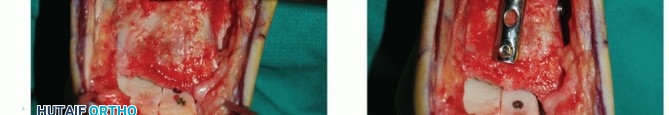

Anterior ankle arthrotomy (TECH FIG 1A)

Open the posterior tibial tendon sheath-flexor retinaculum, directly on the posterior margin of the tibia and medial malleolus (TECH FIG 1B). Protect the posterior tibial tendon: It rests in a groove immediately posterior to the tibia and is at great risk with a medial malleolar osteotomy.

- TECH FIG 1 • A. Medial incision and anterior ankle arthrotomy. B. Opening of the posterior tibial tendon sheath. C. Predrilling of medial malleolus. Kirschner wire for trajectory of medial malleolar osteotomy has already been inserted and its position confirmed with fluoroscopy. D. Fluoroscopic image demonstrating Kirschner wire being used as a guide to direct the saw. E. The periosteum is scored perpendicular to the tibial shaft, at the level of the osteotomy. F. Medial malleolar osteotomy. Care must be taken to protect the posterior tibial tendon. (continued)

Predrill the medial malleolus across the proposed osteotomy site (TECH FIG 1C).

Place a Kirschner wire obliquely to define the trajectory of the medial malleolar osteotomy (TECH FIG 1C).

- TECH FIG 1 • (continued) G. Fluoroscopic image showing near-complete bone cut. H. Release of posterior tibial tendon sheath from distal medial malleolus to allow mobilization.

Determine a plane for the osteotomy in the anteroposterior (AP) plane that is perpendicular to the longitudinal axis of the tibia. We find it helpful to score the osteotomy in the periosteum from anterior to posterior to determine this level (TECH FIG 1E).

With a microsagittal saw oriented correctly in both planes, the osteotomy is initiated (TECH FIG 1F).

Obtain intraoperative fluoroscopy shortly after initiating the osteotomy; leave the saw blade in place to confirm proper trajectory. If incorrect, a subtle adjustment is still possible (TECH FIG 1G).

Continue the osteotomy with the saw to the subchondral bone and then complete the osteotomy with a chisel.

- TECH FIG 2 • A,B. Identifying the extent of the talar shoulder lesion. (continued)

The posterior tibial tendon sheath must be released to the distal aspect of the posterior medial malleolus to allow the malleolus to reflect adequately and to gain optimal exposure of the medial talar dome (TECH FIG 1H). Protect the deltoid ligament fibers. - Preparing the Recipient Site

Define the extent of the OLT (TECH FIG 2A,B).

- TECH FIG 2 • (continued) C-E. Excision of the talar shoulder lesion using the microsagittal and oscillating saws. F. Talar shoulder lesion removed.

Excise the diseased portion of the talus (TECH FIG 2C-F).